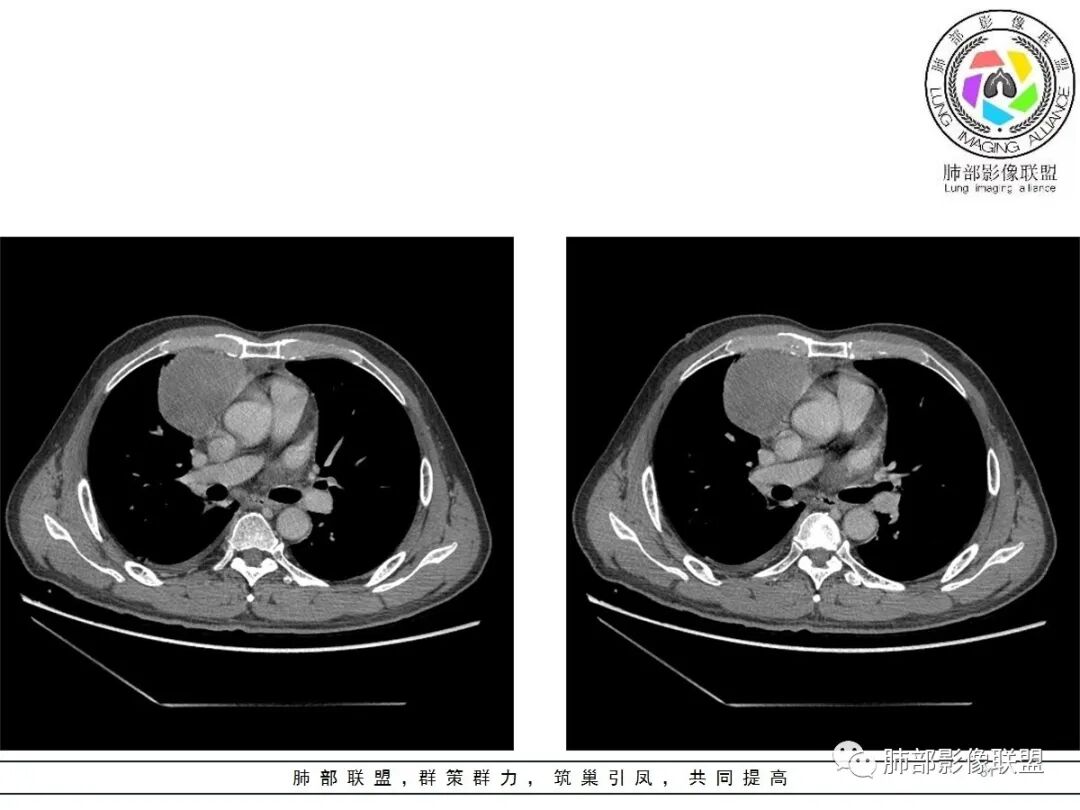

小赵:这个是3月15日的视频

小赵:第二个是3月19日的视频

周围脂肪间隙密度增高,内部小点状很低密度影

右侧少量胸水

19日,4天后, 内部低密度影有,周围渗出增多,胸水增多

2.胸膜掀起,右侧内乳动脉略增粗,定位右前上纵隔内占位。

3.右上纵隔囊实性占位,边界清楚。中央见点状脂肪密度影,边缘见一点状钙化影,增强不均匀环形强化。

4.四天内病灶变化快,块影增大且不规则,包膜似不完整,边界不清,上份可见浸润或渗出,与周围心脏大血管及心包等间隙不清。胸水增多。